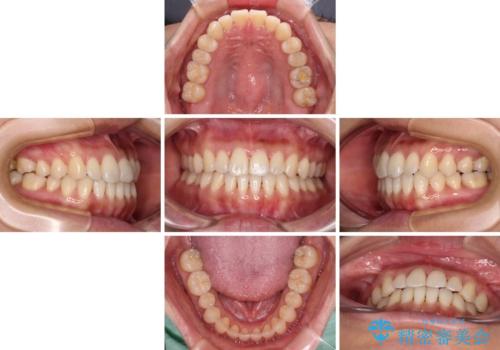

- 前歯のデコボコで前方に出ていることを気にして来院された患者様です。

上顎前歯が捻れて前方に飛び出しており、下顎前歯もそれに沿うようにデコボコとなっていました。

IPR(歯と歯の間を削る処置)によりスペースを獲得して上下顎前歯のデコボコを改善し、飛び出している前歯が引っ込むように設定し、インビザラインにて矯正治療を行うこととしました。

装着時間を守ってくださったので、予定通りの期間で終えることができました。インビザライン特有の、奥歯の咬み合わせの問題もなく、しっかりと歯列を改善することができました。